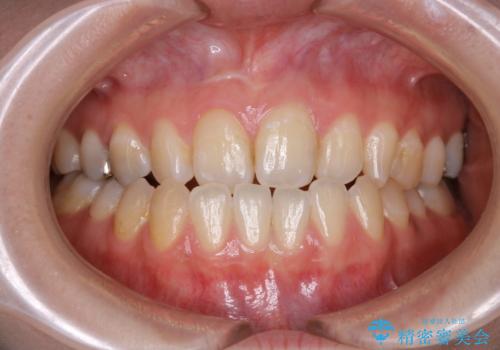

- 受け口で、前歯の嚙み合わせが気になるとの事でご相談にいらした方です。先天的に右上犬歯がなく、左上犬歯も小さい状態でした。矯正治療にて周囲の歯を動かして歯のスペースを確保した上で、被せものにて歯を作っていきました。

歯科技工士さんの熟練した技術により、周囲の歯としっかりなじむ天然歯のような被せ物をお作りすることが出来ました。

矯正治療と補綴治療をうまく組み合わせることで、美しい口元に仕上げることが出来ました。矯正治療、補綴治療をまとめて行える総合歯科治療を体現した治療といえます。